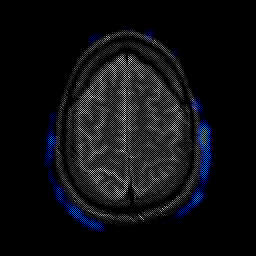

glioma overlay -- Slice #23

[Home][Help][Clinical] Slice 23